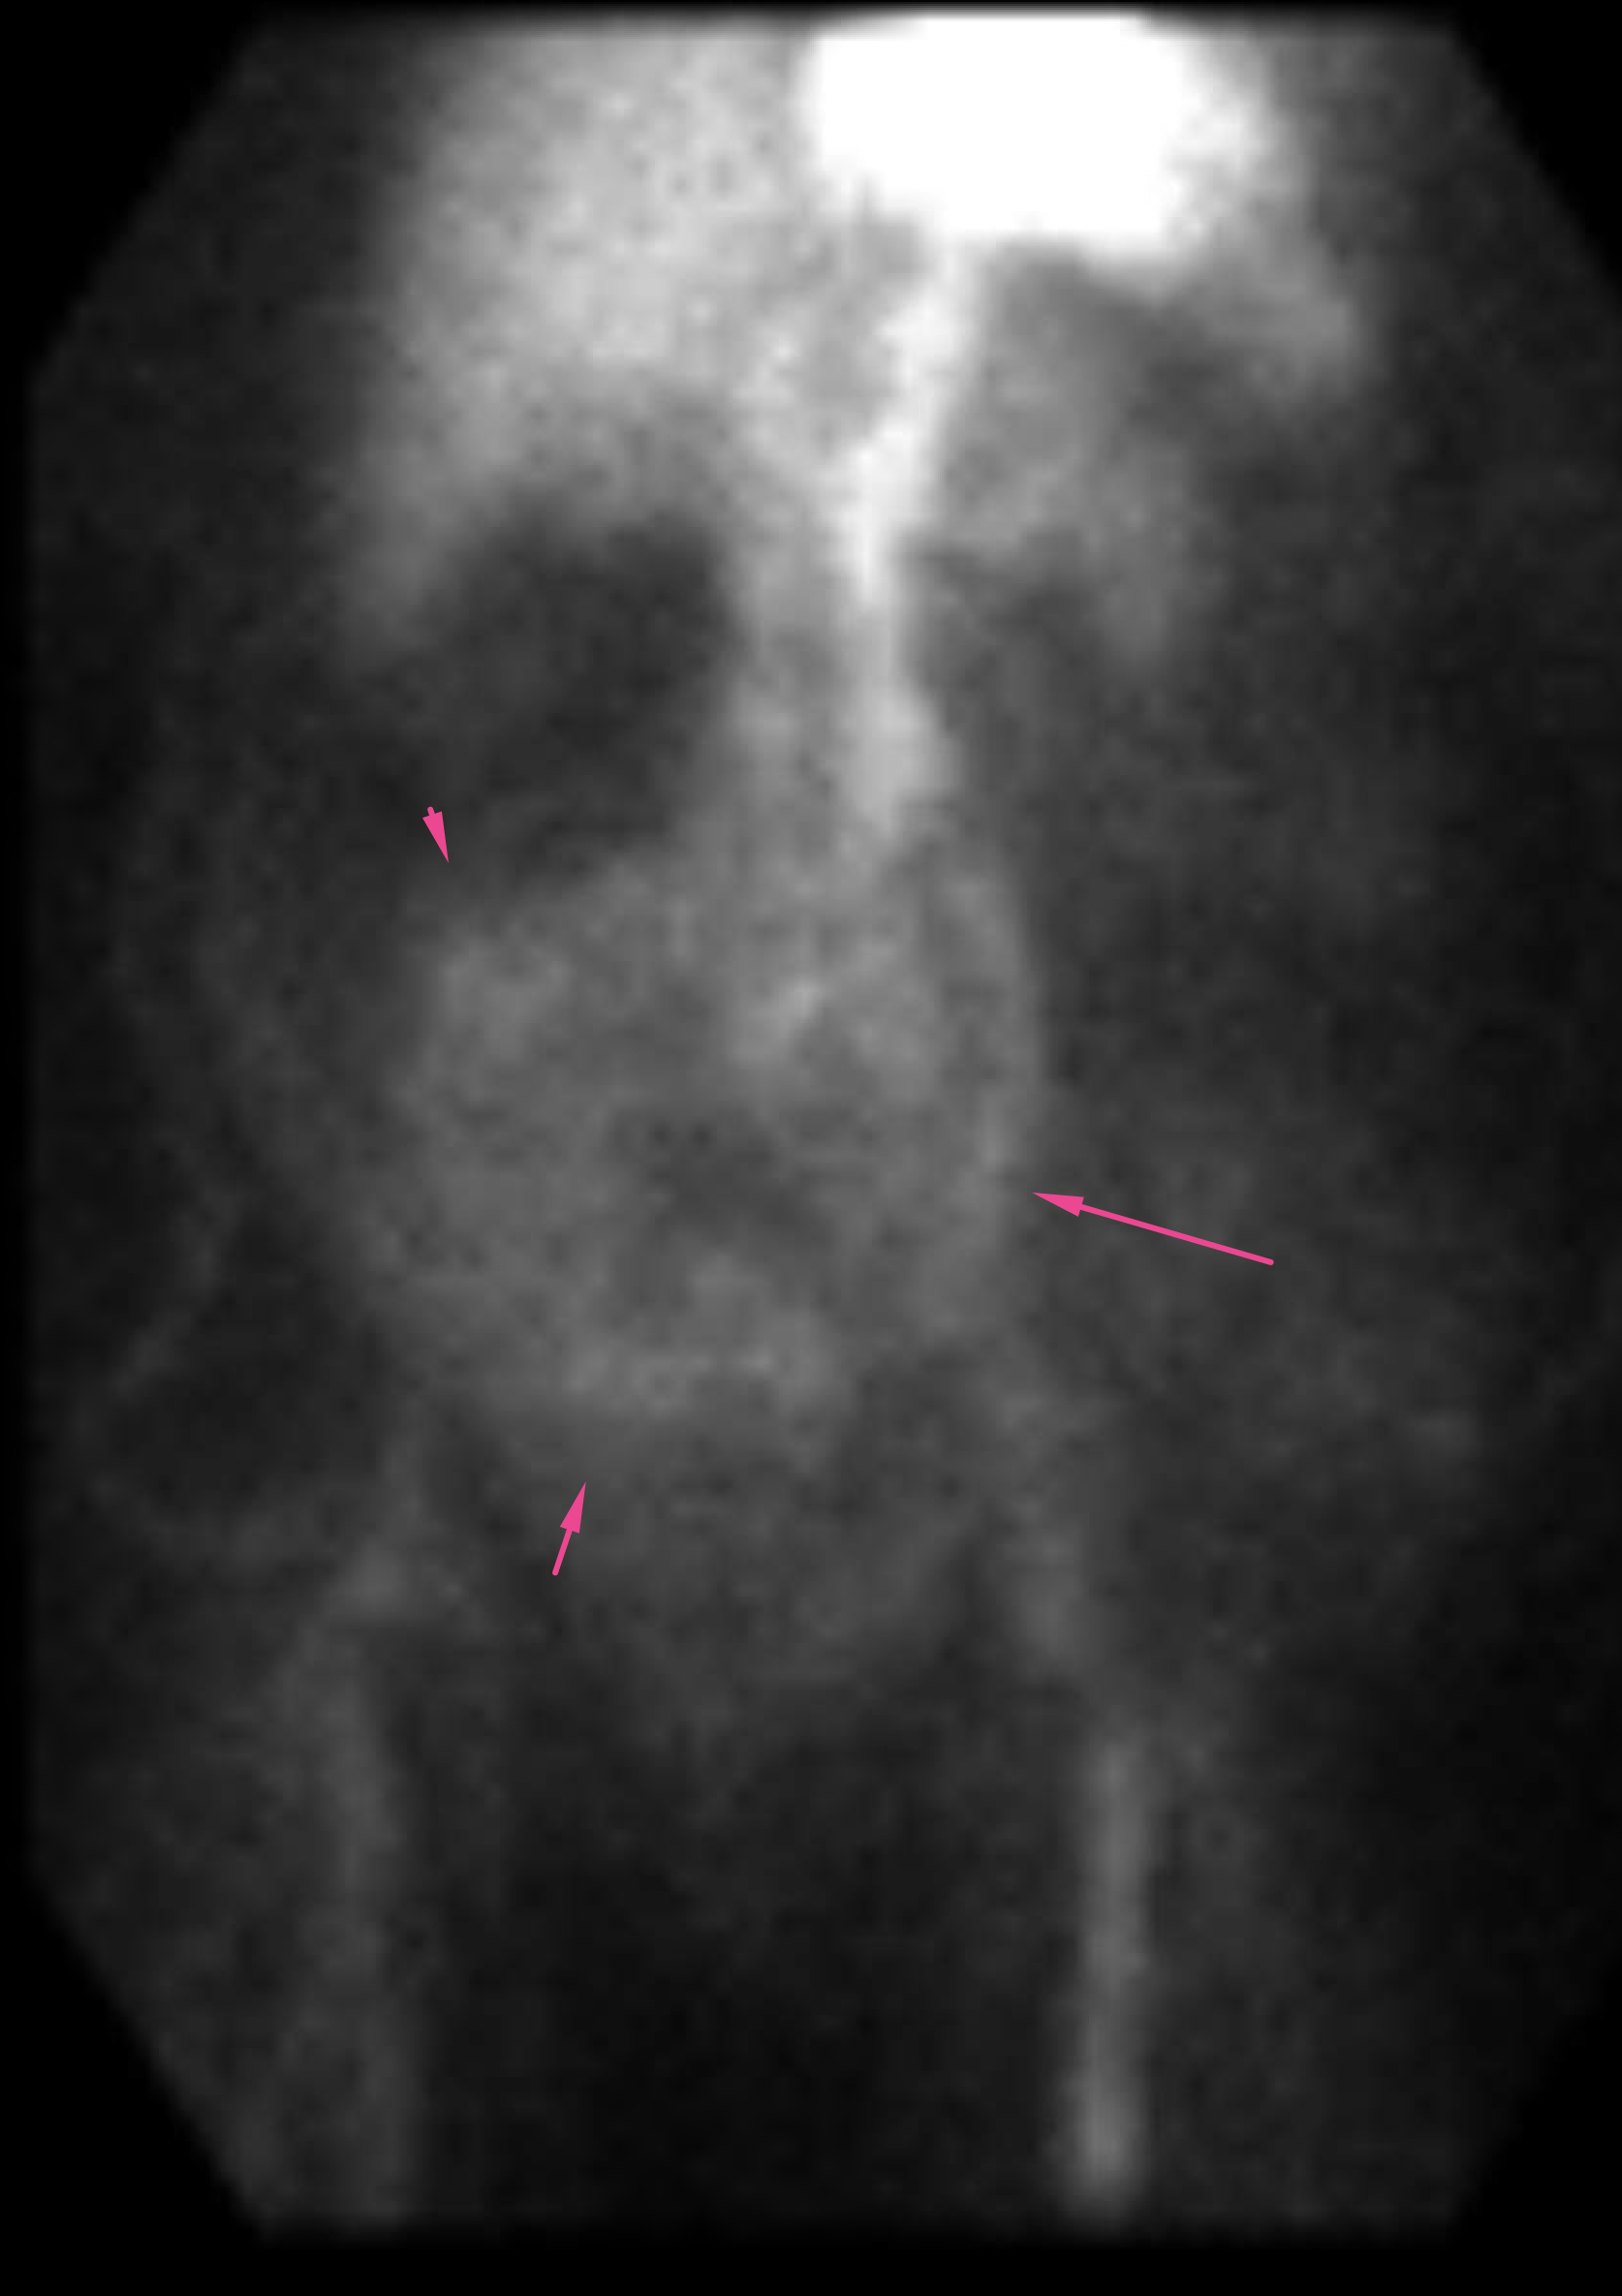

Age: 83

Sex: Female

Indication: GI bleed

Radiotracer: Tc99m labeled RBCs

Sample ReportNo evidence for active GI bleeding during the course of this study.

Hypervascular mass in the lower abdomen and pelvis. Recommend CT for further evaluation if not previously performed.